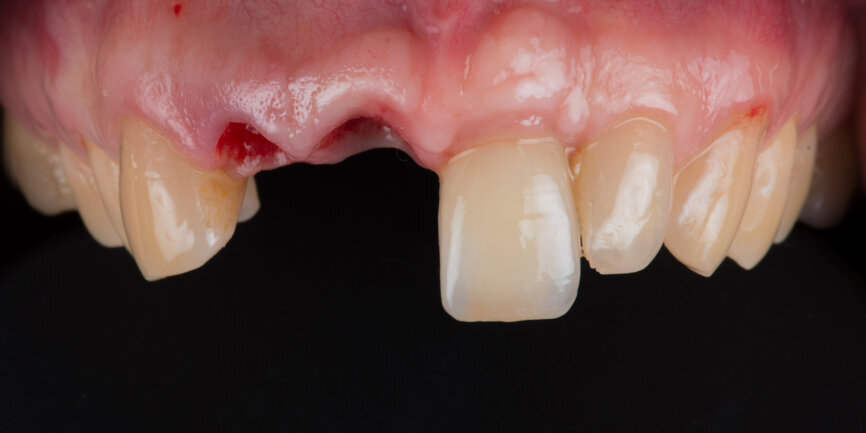

A 52-year-old man, a non-smoker in good general health, was referred after diagnosis of post-traumatic resorption affecting the roots of teeth #11 and #12 (Figs. 1a & 1b). The patient had previously consulted with an endodontist, who stated that both teeth were hopeless and therefore extractions were required. Clinical examination revealed a complete, healthy periodontium around tooth #12 with no sign of infection. At tooth #11, a slight tissue oedema associated with chronic irritation in front of the extensive resorption was observed. The intermaxillary relationship was normal, and the analysis of the smile showed a low smile line (Fig.2). Tooth #21 had been replaced by an implant-supported crown. The previously requested CBCT scan showed that the resorption process was more advanced at tooth #11 (Fig. 3).

Teeth #11 and #12 were diagnosed as hopeless. From a periodontal point of view, the clinical situation was considered favourable for an immediate implant procedure: the gingival margin and papillae were at the same level at these teeth as at the contralateral ones.

Immediate implant procedure for tooth #11

Tooth #11 was extracted atraumatically without raising a flap or performing an osteotomy (Fig. 4). The extraction socket was meticulously cleaned and rinsed with Betadine. The drilling sequence included 2.2, 2.8, 3.2 and 3.7 mm drills (Fig.5). The implant was placed with a final torque of 80 N cm (Figs. 6 & 7). In its final position, the implant platform lay 4 mm below the ideal gingival margin (at the same level of the adjacent implant platform; Fig.8).